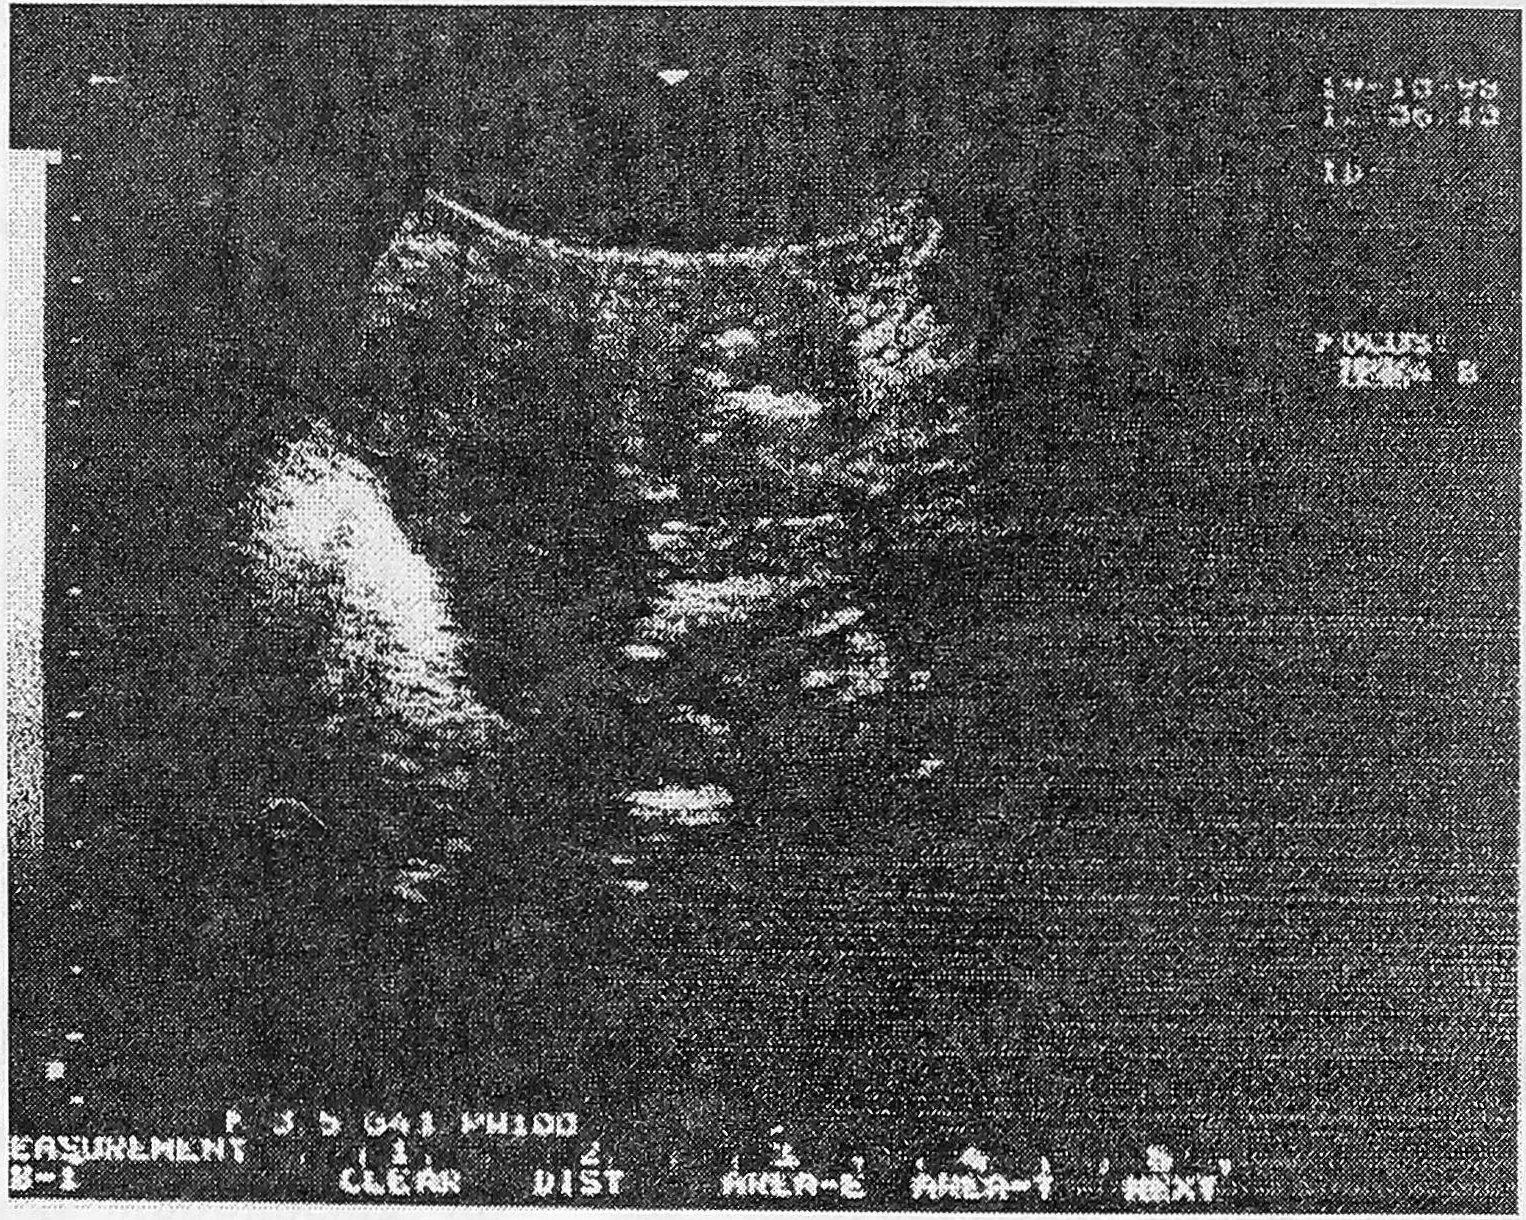

В результате ультразвукового сканирования у 25 женщин с уретритом получены следующие данные: позыв на мочеиспускание у всех женщин появился при ретроградном заполнении мочевого пузыря теплым раствором фурациллина в количестве от 50 до 150 мл (в среднем 98,8 мл), при этом длина уретры (при трансвагинальном сканировании) варьировала от 2,0 до 3,2 см (в среднем 2,57 см), ширина составляла от 0,3 до 1,0 см (в среднем 0,67 см). Форма уретры была разной: овальная у 16 (64,0% ±12,0) женщин, воронкообразная у 6 (24,0% ±17,4), колбообразная у трех (12,0%±18,7) (рис. 1, 2, 3). При стандартном заполнении мочевого пузыря (150-250 мл) образование цистоуретральной воронки наблюдалось у двух (8,0%±19,1) женщин, при этом отмечено укорочение уретры на 0,2-0,5 см (в среднем на 0,32 см), что находится в рамках физиологических колебаний. Проба Маршала во всех наблюдениях была отрицательной, т.е. недержания мочи при заполнении мочевого пузыря не было у всех пациенток. Остаточная моча в количестве 30,0 мл определялась лишь у одной пациентки, у которой помимо признаков уретрита имел место и острый цистит, эхографически видный как утолщение стенок мочевого пузыря и яркого свечения полости слизистой мочевого пузыря (рис. 4).

Рис. 2. УЗ-сканирование уретры (воронкообразная уретра).